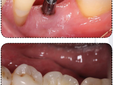

Questi bio-ingegneri, grazie anche ai sistemi odierni di tecnologia 3D CAD-CAM, sono riusciti a mettere a punto una nuova tecnica di rigenerazione ossea in ambito odontoiatrico. Rompendo tutti gli schemi attuali utilizzati dai dentisti fino ad oggi, si è riusciti a far ricrescere l’osso in grandi quantità, nel caso più estremo 16mm in altezza nella mandibola, permettendo così di poter collocare impianti dove prima era impossibile. Queste barriere sono costruite su misura, individualizzando così il trattamento per ogni paziente, rigenerando osso nelle giuste quantità, in base al piano di trattamento scelto insieme dal paziente ed il dentista, così facendo sarà, in alcuni casi, possibile collocare la barriera insieme agli impianti, accorciando cosi a 5 mesi circa il tempo necessario per rigenerare e preparare la protesi provvisoria, il tempo si allunga a 10/11 mesi quando si è costretti a rigenerare prima di poter collocare gli impianti.

Un altro utilizzo di queste barriere è quello di rigenerare osso intorno a impianti che hanno sofferto una periimplantite, ovvero quella malattia che provoca la perdita di osso intorno gli impianti, compromettendo cosi il loro funzionamento. Questo, fino ad oggi, non aveva cura, obbligando cosi i pazienti a spendere un’ingente quantità di soldi per estrarre gli impianti non più utilizzabili, collocarne dei nuovi e poi costruire una nuova protesi. Con queste barriere, invece, è possibile recuperare gli impianti già presenti nella bocca del paziente, operazione molto più economica, e poi costruire una sola nuova protesi. Insomma la tecnologia avanza e con questo anche la scienza, migliorando sempre di più la vita delle persone.